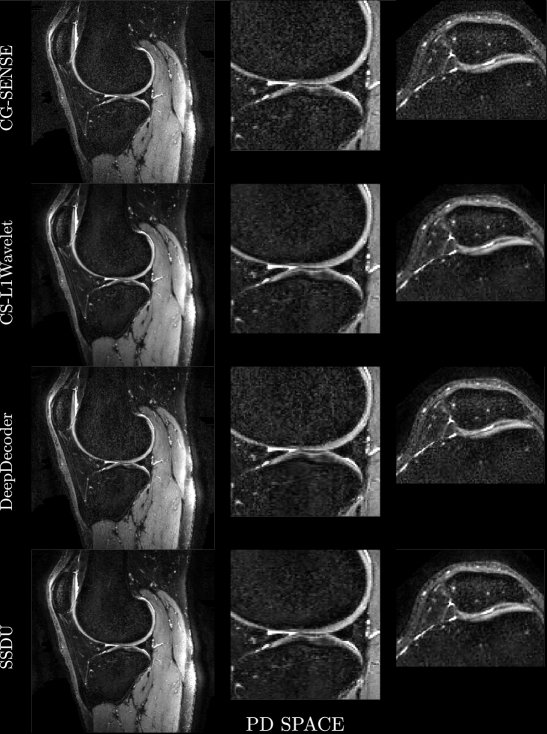

Figures 4, 5 show axial MPRAGE brain slices at the different field strengths and corresponding closeups of the cerebellum and the left frontal lobe. Figure 6 shows a sagittal PD knee slice (3T) with closeups of articular cartilage interfaces in sagittal (femur) and axial (patella) views. These show the generalizability of the methods to different magnetic field strengths as well as changes in anatomy and contrast. Example reconstructions for the other sequences can be found in the Appendix 8, 9.

Qualitatively, we can see from Figures 4, 5, 6 that all methods are able to generalize well (in the sense of approximately preserving performance/appearance on dataset used for training/tuning) to changing field strengths, anatomy, and contrast, although changing anatomy clearly worsened absolute image quality as compared to changing field strength. DeepDecoder preserves its spatially varying smoothing/artifacts, and SSDU/CS-L1Wavelet are able to produce images with less noise and comparable sharpness to CG-SENSE, although CS-L1Wavelet exhibits more artifacts. As expected, the perceptual quality of all methods increase with increasing field strength due to higher spatial resolution. Differences between the methods are less pronounced in the knee scan although overall image quality is worse.

In the second row of Figure 7, we show bar plots of the scores from the MR scientists and the radiologist; we pooled the scores of the MR scientists. We see that MR scientists and the radiologist generally agree for evaluating SNR, aliasing, and overall quality, rating CS-L1Wavelet/SSDU as being better than or the same as CG-SENSE/DeepDecoder. We recall that lower ratings correspond to better quality. MR scientists rated CS-L1Wavelet/SSDU with a mean overall quality of (2.09/1.97) as compared to CG-SENSE/DeepDecoder with (2.96/3.57). The radiologist rated CS-L1Wavelet/SSDU with a mean overall quality of (2.73/2.23) as compared to CG-SENSE/DeepDecoder with (3.63/3.87). We note that for both sets of raters, the difference between CS-L1Wavelet and SSDU in overall image quality was found to not be statistically significant. Furthermore, when we restrict our analysis to the average score change between the subgroup of changes in field strength vs. the subgroup of PD Knee/ Knee scans, the overall image quality rating of CG-SENSE/CS-L1Wavelet/DeepDecoder/SSDU all worsen in the knee scans for the MR scientists, with increases of 0.26,0.40,0.11, and 0.79 respectively. In contrast, for the radiologist, this shift results in changes of -0.33,0.33,-0.16, and 0.83 respectively, indicating that only CS-L1Wavelet and SSDU worsened.